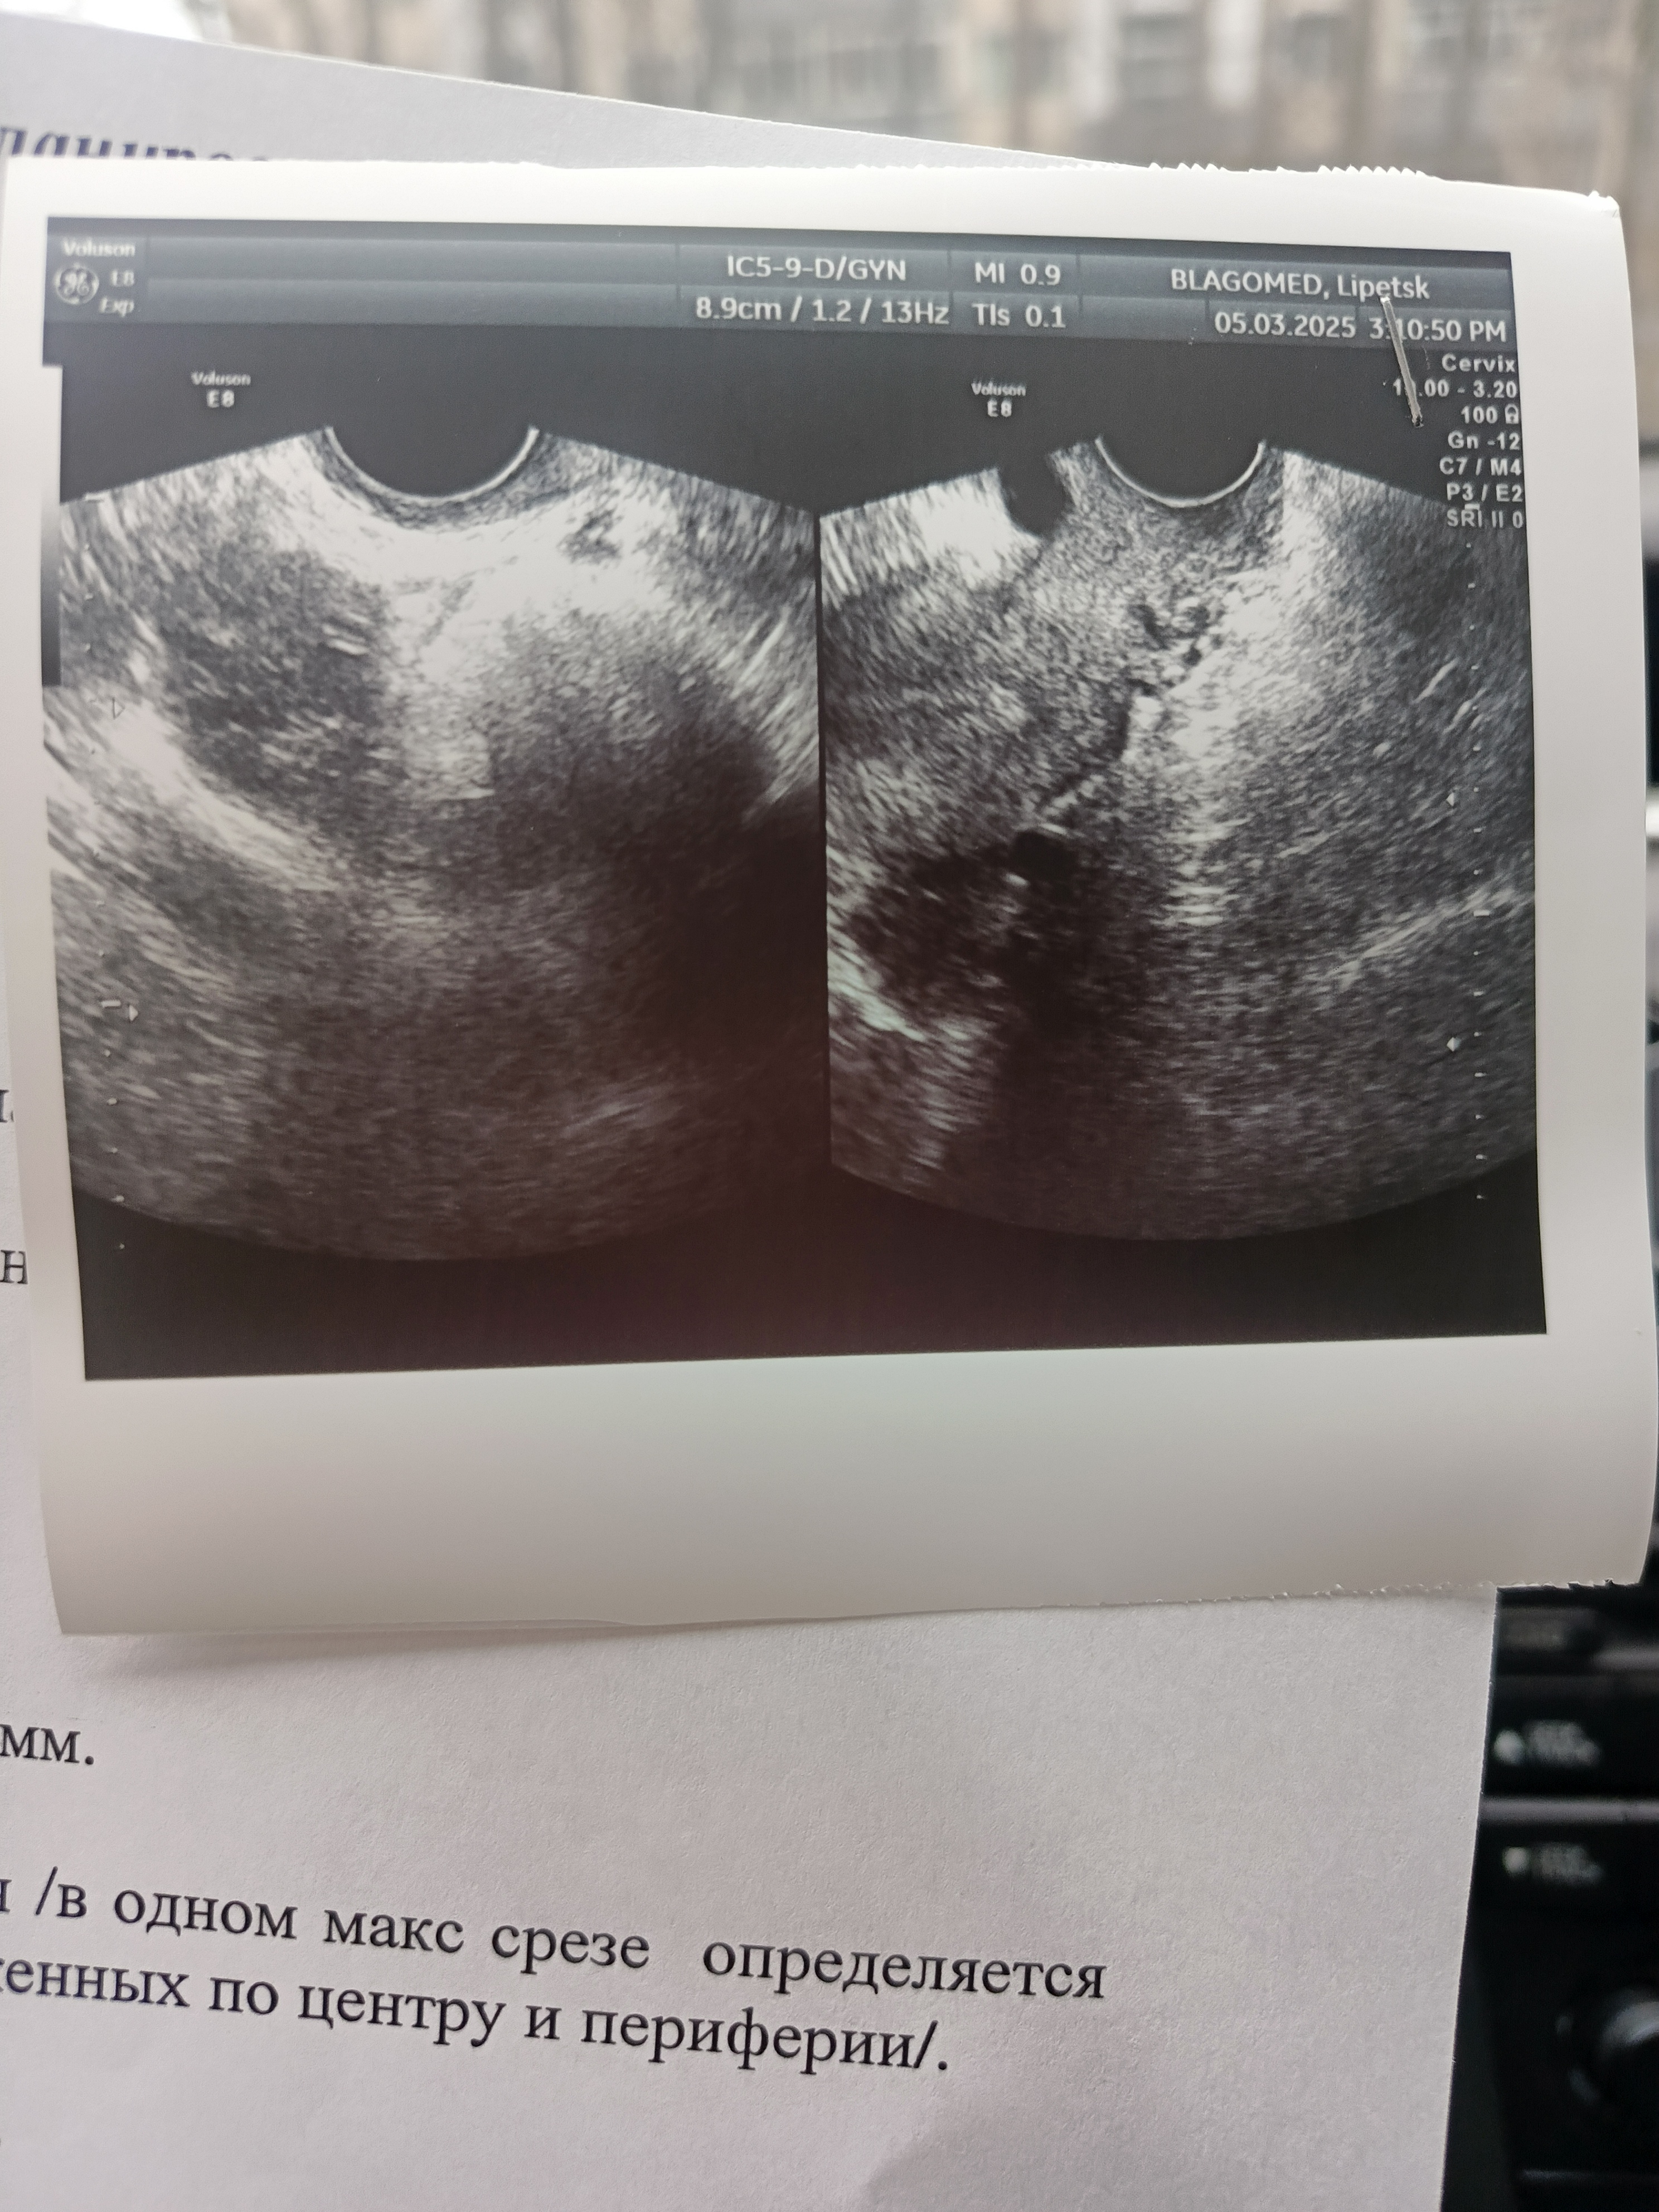

Девочки а что за кружки на узи с права? Не может быть беременность?

Если бы была беременность, то вам написали бы в заключении. Скорее всего фолликул.

Фолликулы, скорее всего

Настасья Я, просто сделала узи и передала, к врачу пока не ходила, а сейчас разглядывала и не понимаю что за дырочки так сказать в правом снимке 🤭 стало интересно решила задать вопрос)))

Яна Алексеева, я ничего не спрашивала мне нужно просто узи для врача, а она там по своему болтала, я думаю она бы правда написала если что было бы, просто дома начала рассматривать не понятны эти дырочки были.

Виктория , для врача снимки неинформативны, он будет читать заключение, так могут выглядеть и сосуды, и кисты, и плодное яйцо, по фотографии гадать он не будет.